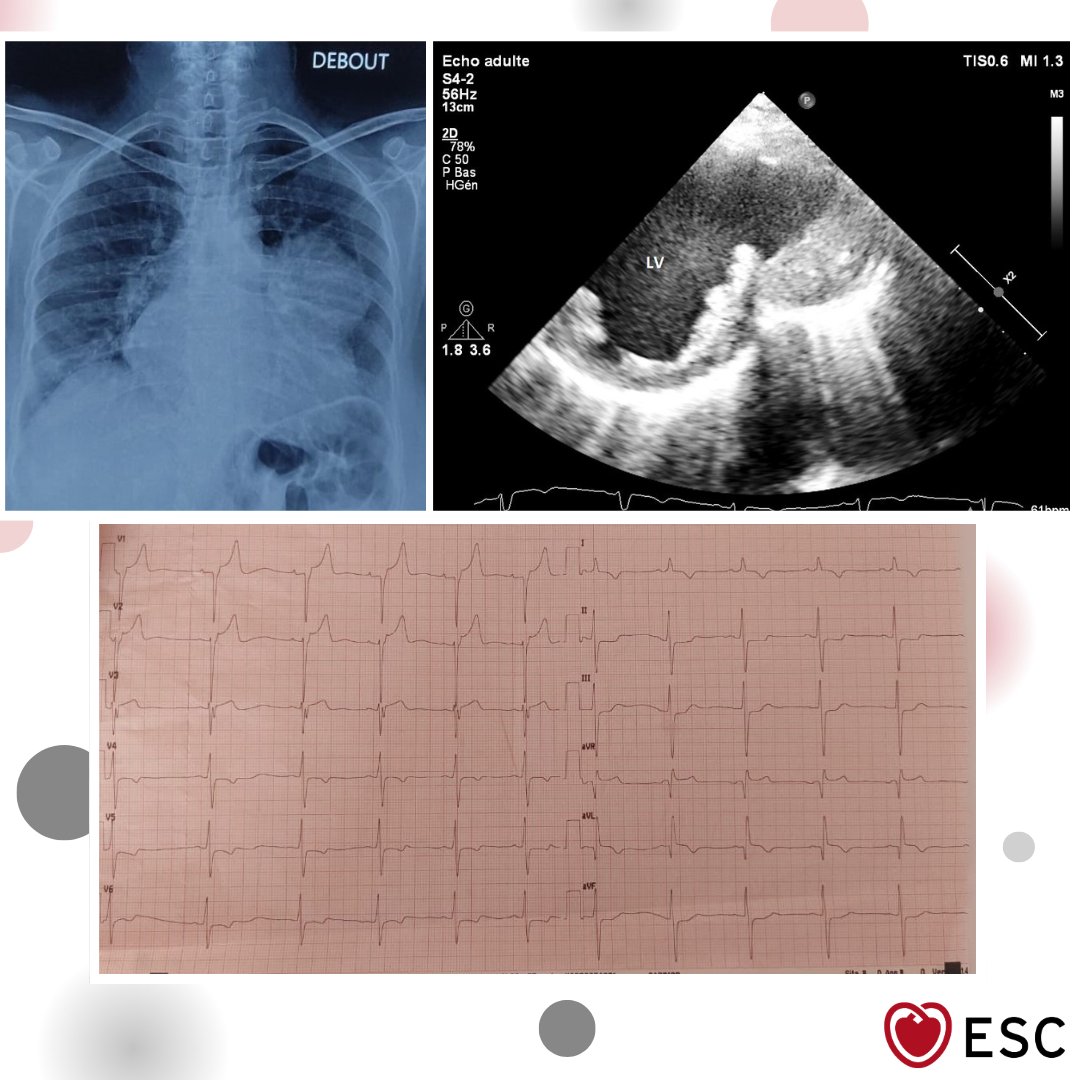

#ImageOfTheWeek by Nabil Laktib, Lydia Yasmine Nnomo, and Zouhair Lakhal from the Cardiology Intensive Care Unit, Mohammed V Military Teaching Hospital, Rabat, Morocco. A patient in their 60s presented with a late-presentation ST-elevation myocardial infarction. What is the…

escardio's tweet image. #ImageOfTheWeek by Nabil Laktib, Lydia Yasmine Nnomo, and Zouhair Lakhal from the Cardiology Intensive Care Unit, Mohammed V Military Teaching Hospital, Rabat, Morocco. A patient in their 60s presented with a late-presentation ST-elevation myocardial infarction. What is the…